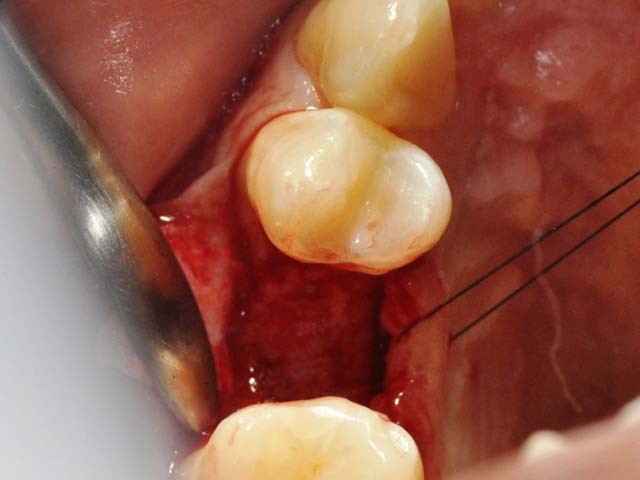

齒槽骨保存術+植牙 首頁 案例分享 人工植牙 齒槽骨保存術+植牙 STEP1拔除掉無法使用的斷裂牙根 STEP2齒槽骨保存術—使用骨粉填補拔牙傷口 術前 V.S 術後 植牙第一階段—植入牙根 植牙第二階段—製作正式假牙